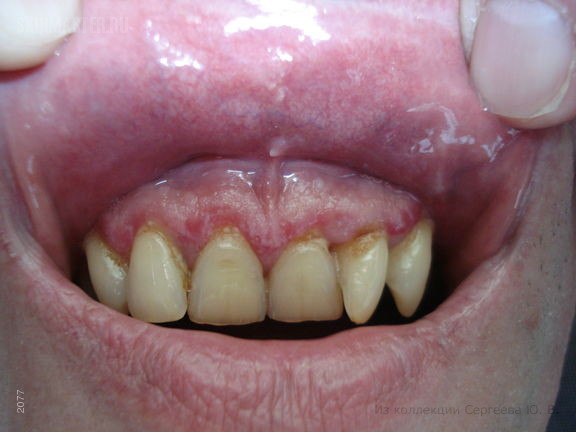

Красный плоский лишай десен

При осмотре: в области десен слизистая слегка отечна и гипертрофирована, имеются очажки белесоватого цвета образующие кружевной рисунок.

Клинический диагноз